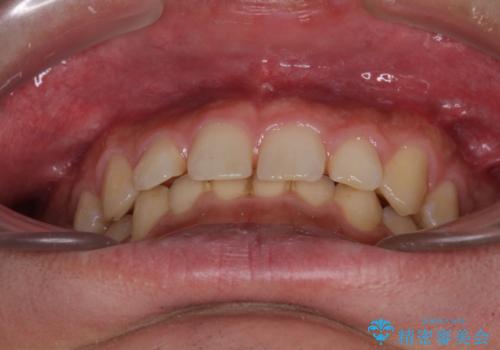

- 前歯の隙間と深い咬み合わせを改善したいとのことで来院された患者様です。

マウスピース矯正の自己管理が面倒とのことで、ワイヤー矯正により治療を行うこととしました。

奥歯の咬み合わせは理想的な状態であったため、ワイヤー矯正でもインビザラインでも比較的容易に対応可能でした。